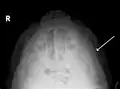

Fracture of the zygomatic arch as seen on plain X-ray